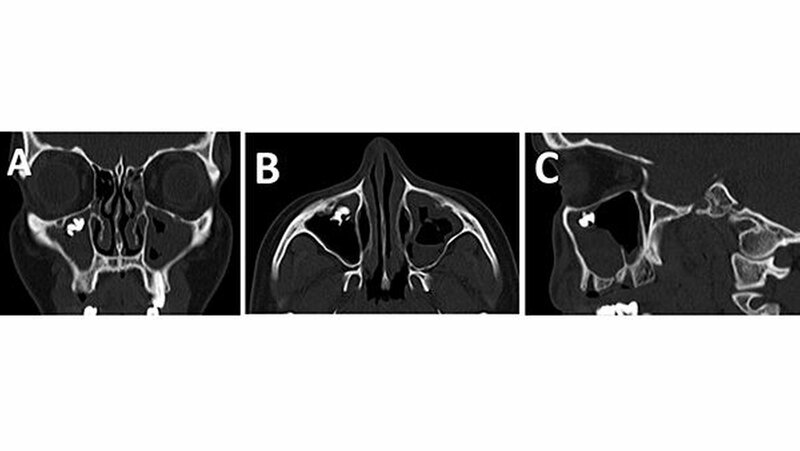

Das angefertigte Orthopantomogramm (OPT) stellte den aktuellen Zahnstatus mit dem Nebenbefund einer röntgendichten Verschattung im Sinne eines Fremdkörpers unterhalb des rechten Kieferhöhlendachs dar (Abbildung 1). Es folgte die Anfertigung eines NNH-CT zur genauen Lokalisierung des Fremdkörpers (Abbildung 2) für die anschließende OP-Planung.

In unserem Fall zeigte sich der röntgenopake Fremdkörper im OPT als Zufallsbefund. Zur genauen Lokalisation ist jedoch eine zwei- bis dreidimensionale radiologische Darstellung notwendig [Ferguson, 2014]. Bei der zweidimensionalen Darstellung bietet sich zum OPT ein Fernröntgenseitenbild und bei der dreidimensionalen ein DVT, NNH-CT sowie im Fall von nicht ferromagnetischen Fremdkörpern auch ein MRT an.